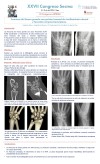

Rotura cerrada del ligamento transverso intermetacarpiano profundo

Claudia González García, Sabina Cañada Oya, Belén García Medrano, Sara Márquez Martínez